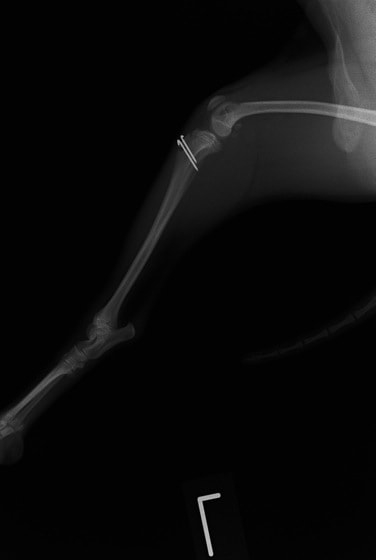

■ 症例20 ポメラニアン 8ヶ月 1.8kg

左右膝蓋骨脱臼 グレードⅢ

2ヶ月前から間欠的跛行が認められ、両膝の膝蓋骨脱臼整復術を行った。

手技は縫工筋及び内側広筋の解放、脛骨粗面の外側転位、滑車ブロック形造溝術、内外側関節包の縫縮を選択し実施した。

右側の膝蓋骨脱臼は上記手技で整復されたものの、左側はそれのみでは膝蓋骨が浮く様子が認められた。その為、PDS縫合糸にて膝蓋靱帯を1糸のみ縫合し、靱帯の縫縮を行った。